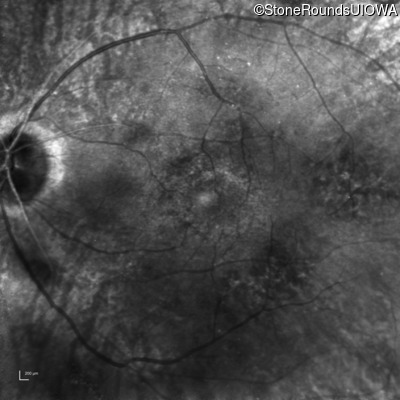

Infrared Fundus Photograph - Left - 20/25 -1

Exemplar